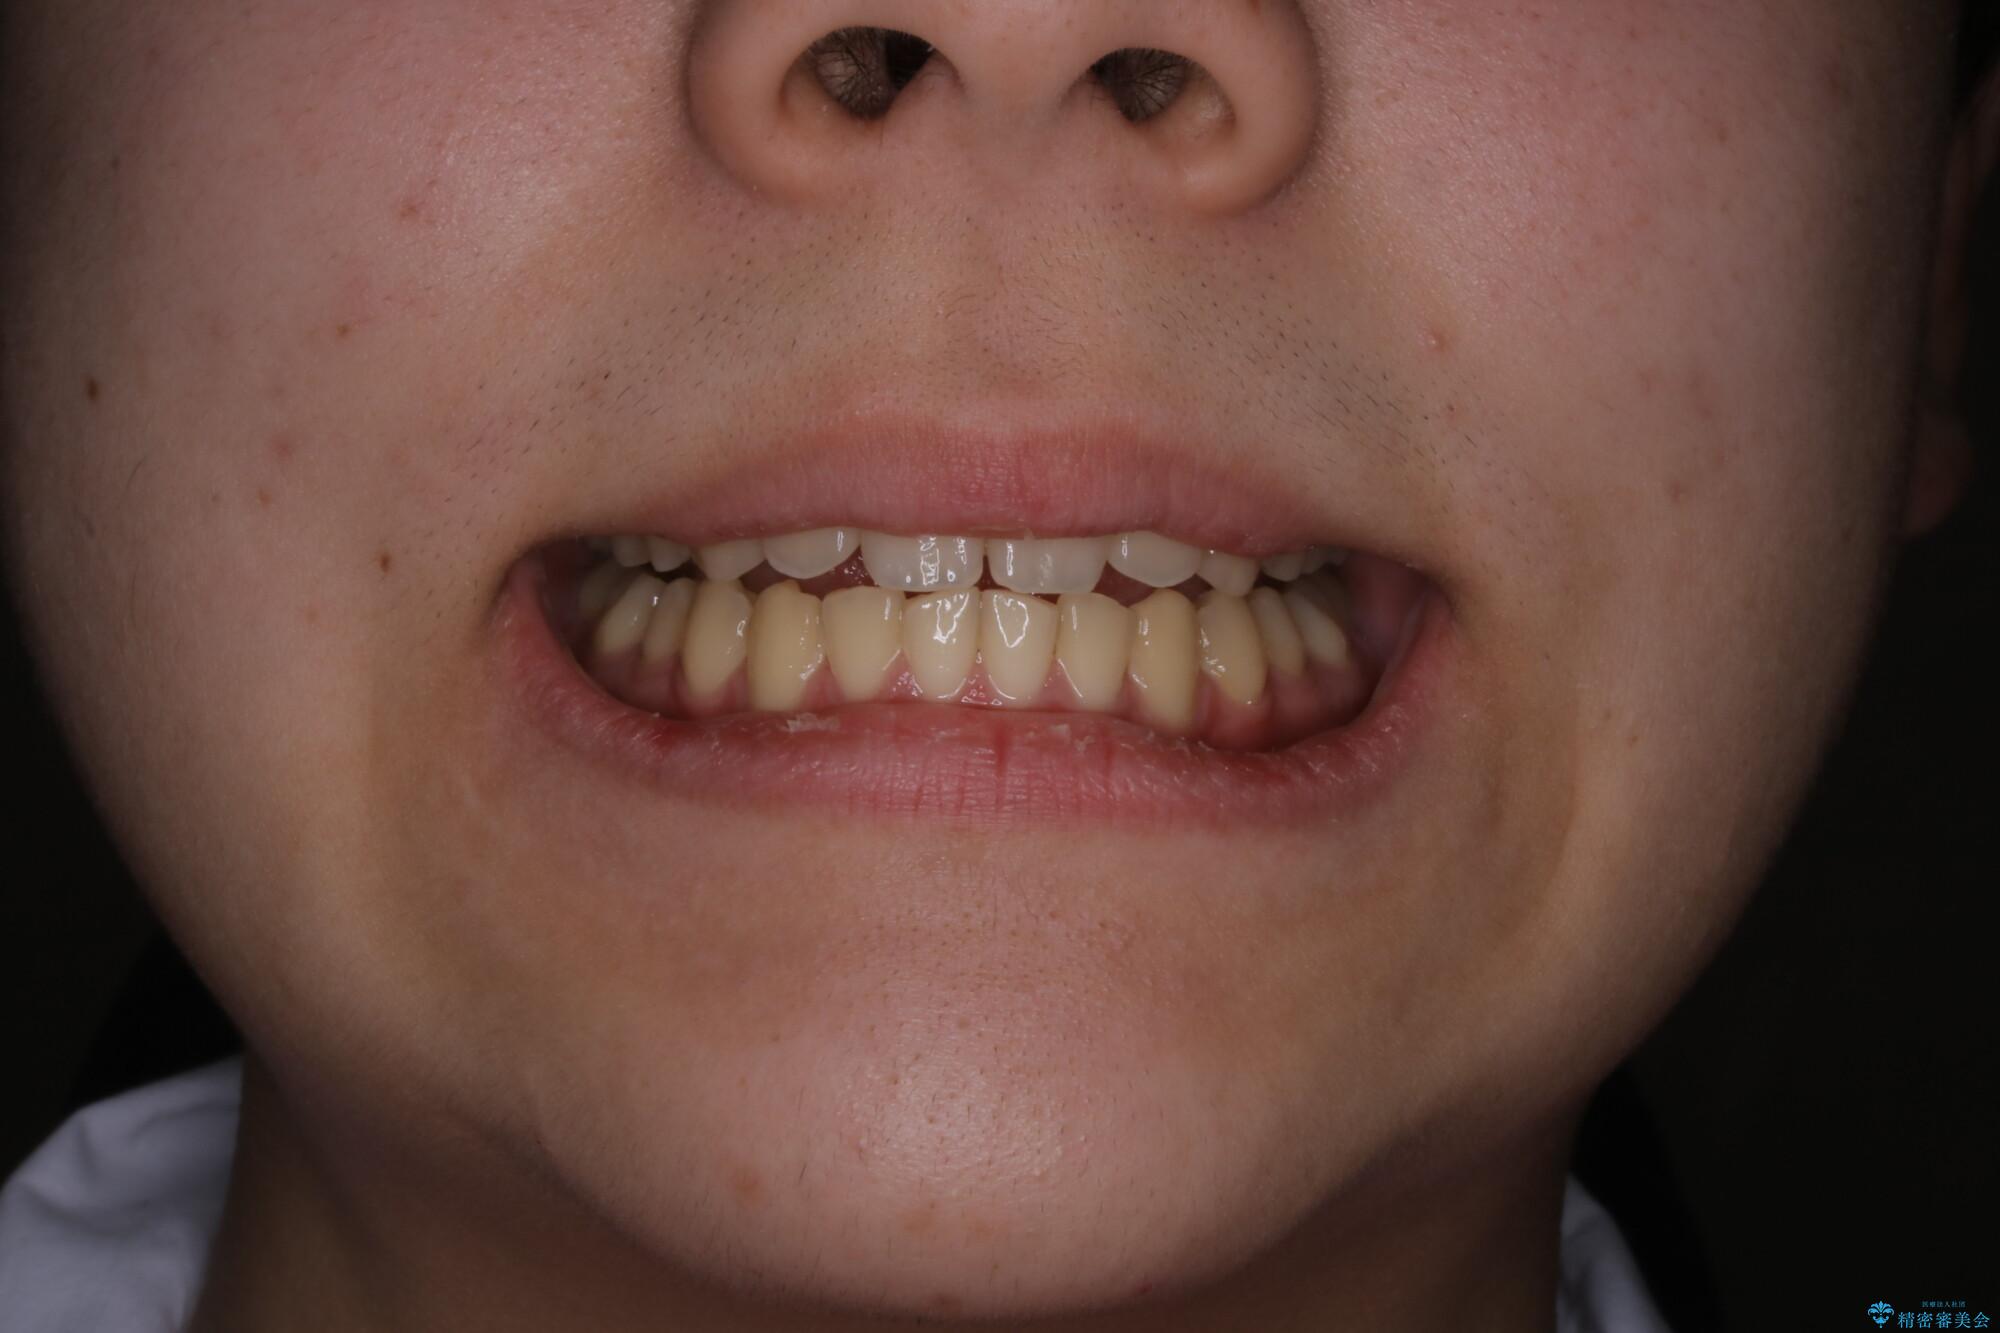

- 患者様、出っ歯のお悩みで来院されました。

骨格の分析を行ったところ上顎も出てはいるのですが、下顎が引っ込んでいる状態であるということがわかりました。

よって上顎の歯を抜いて治療をするのではなく、カリエールという器具を使用して下顎を前に引っ張り出しながら上顎を引っ込めるという治療を行うことにしました。

ひと口に出っ歯(上顎前突)といっても原因は多様です。

骨格的な問題があるのか、歯だけの問題なのか、上顎が出ているのか、下顎が出ているのか。あるいはその両方か。

きちんと原因を見極めたうえで治療を開始しないと仕上がりは理想的になりません。

矯正検査を行い、しっかりと矯正診断を行った上で治療を開始することが大事です。